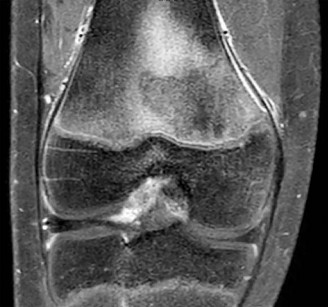

An 8-year-old Japanese girl presents with a painless, palpable 'clunk' on the lateral side of her left knee during terminal extension. MRI confirms a discoid lateral meniscus. Which specific variant of a discoid meniscus is characterized by an absent posterior meniscotibial attachment, leading to hypermobility and snapping?